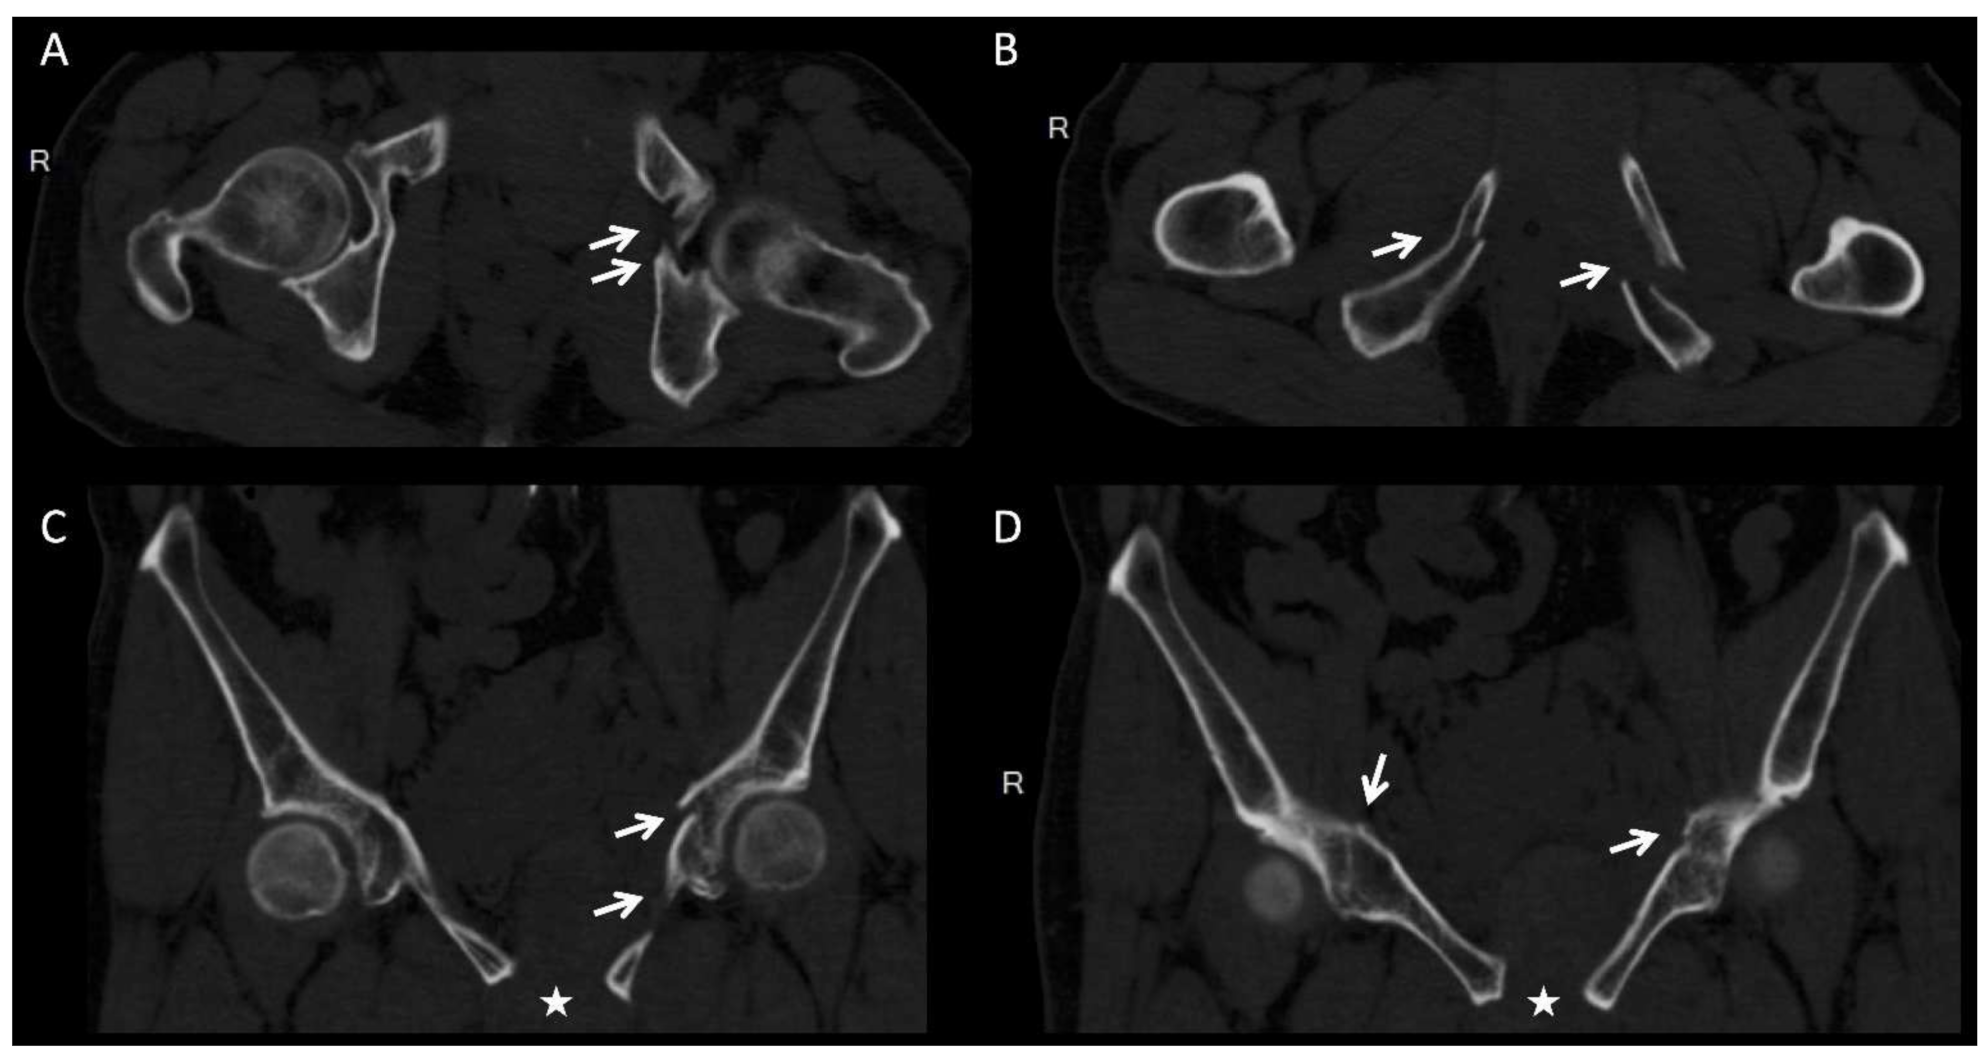

- Hung, C.C.; Li, Y.T.; Chou, Y.C.; Chen, J.E.; Wu, C.C.; Shen, H.C.; Yeh, T.T. Conventional plate fixation method versus pre-operative virtual simulation and three-dimensional printing-assisted contoured plate fixation method in the treatment of anterior pelvic ring fracture. Int. Orthop. 2019, 43, 425–431. [Google Scholar] [CrossRef] [PubMed]

- Hsu, C.L.; Chou, Y.C.; Li, Y.T.; Chen, J.E.; Hung, C.C.; Wu, C.C.; Shen, H.C.; Yeh, T.T. Pre-operative virtual simulation and three-dimensional printing techniques for the surgical management of acetabular fractures. Int. Orthop. 2019, 43, 1969–1976. [Google Scholar] [CrossRef]